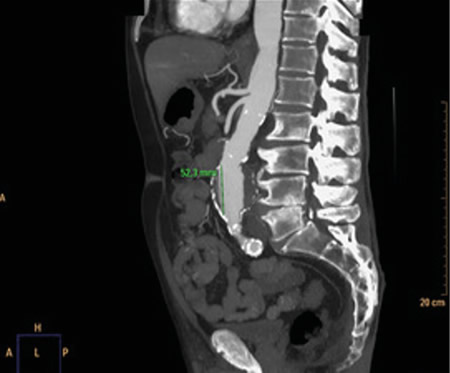

Respecto a las pruebas complementarias, en la analítica sanguínea, se halla una PCR de 39,1 mg/l, leucocitosis de 21.300/mm3, con 88 % de neutrófilos, y una hemoglobina de 10,5 g/dl. En la radiografía pélvica no se evidencian hallazgos patológicos. Debido a la hipotensión, se decide realizar un TC abdominal (Figuras 1 y 2), en el que se objetiva un aneurisma de aorta infrarrenal roto, con diámetro de 50 x 52 x 48 milímetros, a 50 mm de arteria renal derecha y a 65 mm de arteria renal izquierda, craneal a la bifurcación ilíaca. Asimismo, se aprecia un hematoma retroperitoneal en contexto de sangrado en parte posterior de la aorta, que infiltra el músculo psoas ilíaco izquierdo, justificando la clínica de coxalgia con irradiación izquierda. Se contacta con cirugía vascular, interviniéndose de forma urgente, con buena evolución posterior.

Fig. 1. TC coronal de aneurisma de aorta abdominal.

Fig. 2. TC transversal de aneurisma de aorta abdominal.